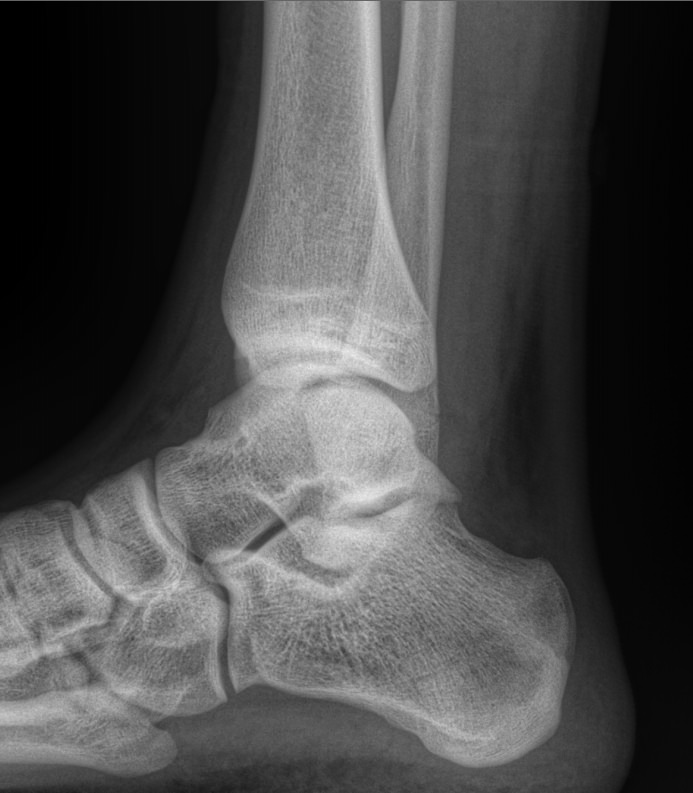

Сустав, соединяющий голень и стопу, наряду с коленным, выполняет важные функции перемещения тела в пространстве и поднятия собственного веса. Голеностоп имеет сложное строение и, как и любой другой сустав в теле человека, подвержен системным заболеваниям и травмам.

В диагностике патологий голеностопных суставов рентгеновское исследование относится к скрининговым, то есть первичным, методам. Действительно, рентген ― классический, простой, доступный и безболезненный способ получить информацию о внутреннем строении и патологических изменениях, произошедших в суставе. А благодаря современным цифровым аппаратам исследование становится и практически безопасным, так как несет минимальную дозу облучения.

Что покажет рентген голеностопного сустава

В описании врач указывает патологические изменения, если они есть в следующих образованиях:

• Суставные щели;

• Соответствие друг другу суставных поверхностей;

• Костная ткань и надкостница;

• Мягкие ткани.

Также подробно описываются переломы, вывихи, новообразования, их местоположение и особенности.